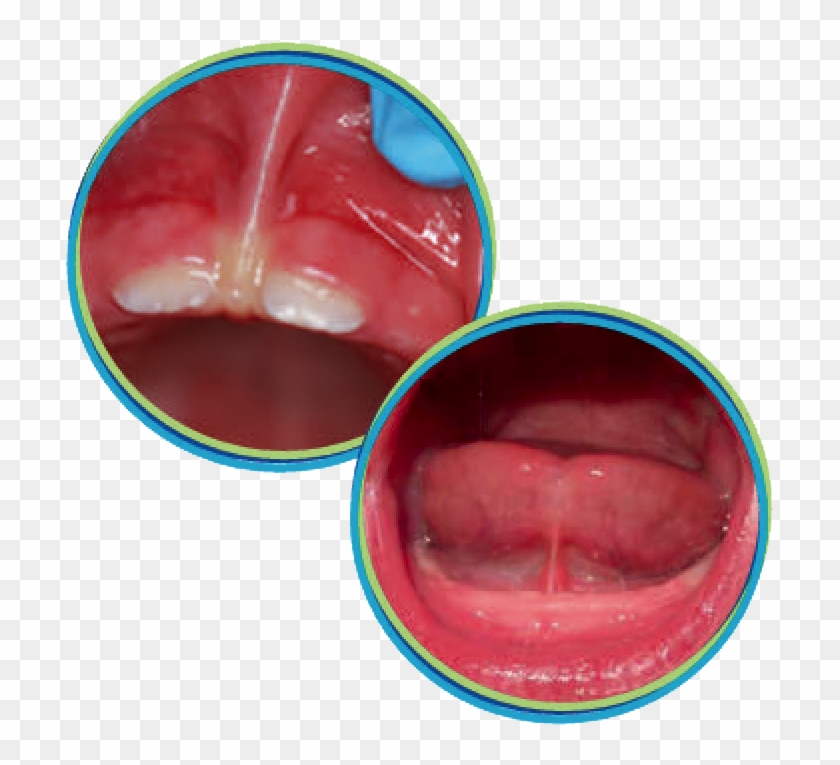

Lip & Tongue Tie Revision: Before & After Photos of Baby’s Frenectomy …

Tongue Tie: Before and After Photos